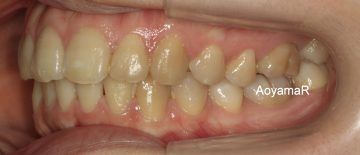

過蓋咬合(かみ合わせが深い、オーバーバイト)の矯正症例

CASE 15

(20歳 女性 )

マウスピース型カスタムメイド矯正装置(インビザライン)単独による治療

治療後